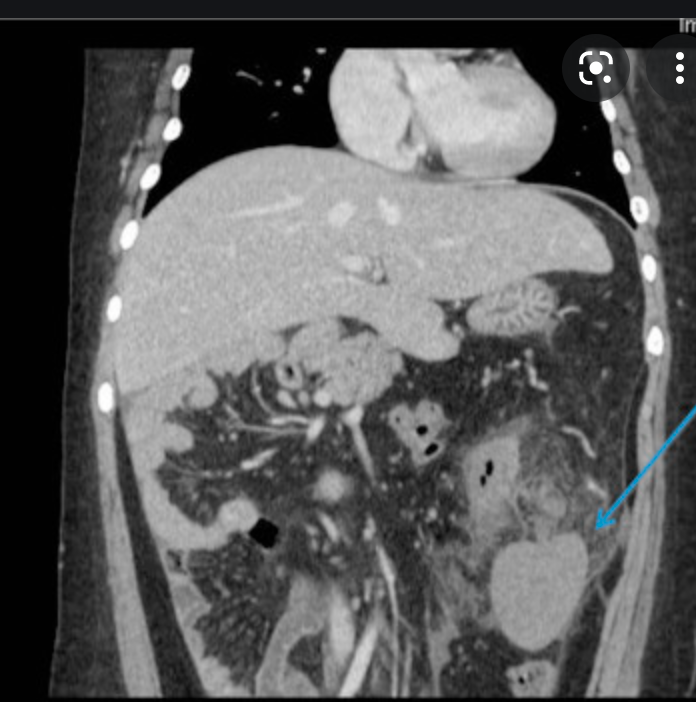

Wandering Spleen

Wandering spleen is a rare condition in which the spleen migrates from its usual anatomical position, commonly to the lower abdomen or pelvis.

Wandering spleen is rare, with a reported incidence of <0.5%.

Diagnosis is most commonly made between ages 20 and 40 years and is more common in multiparous women 1,6.

Wandering spleen can be an elusive diagnosis as its presentation is greatly variable and intermittent torsion can cause non-specific signs and symptoms.

It can present as an asymptomatic or painful abdominal mass, intermittent abdominal pain, or as an acute abdomen (e.g. bowel obstruction, acute pancreatitis) 3,4,6.

The abnormal mobility of the spleen is caused by an abnormality of its suspensory ligaments. There may be a congenital absence or underdevelopment of these ligaments, or an acquired laxity of the ligaments caused by various conditions, such as pregnancy or diseases causing splenomegaly. Due to these abnormal ligaments a long vascular pedicle may form, containing the splenic vessels, predisposing the spleen to torsion and consequently splenic infarction 4.

The often non-specific clinical presentation of wandering spleen makes radiological evaluation invaluable in its diagnosis. Performing the radiological investigations in different positions allows identification of the wandering spleen’s inclination to wander.